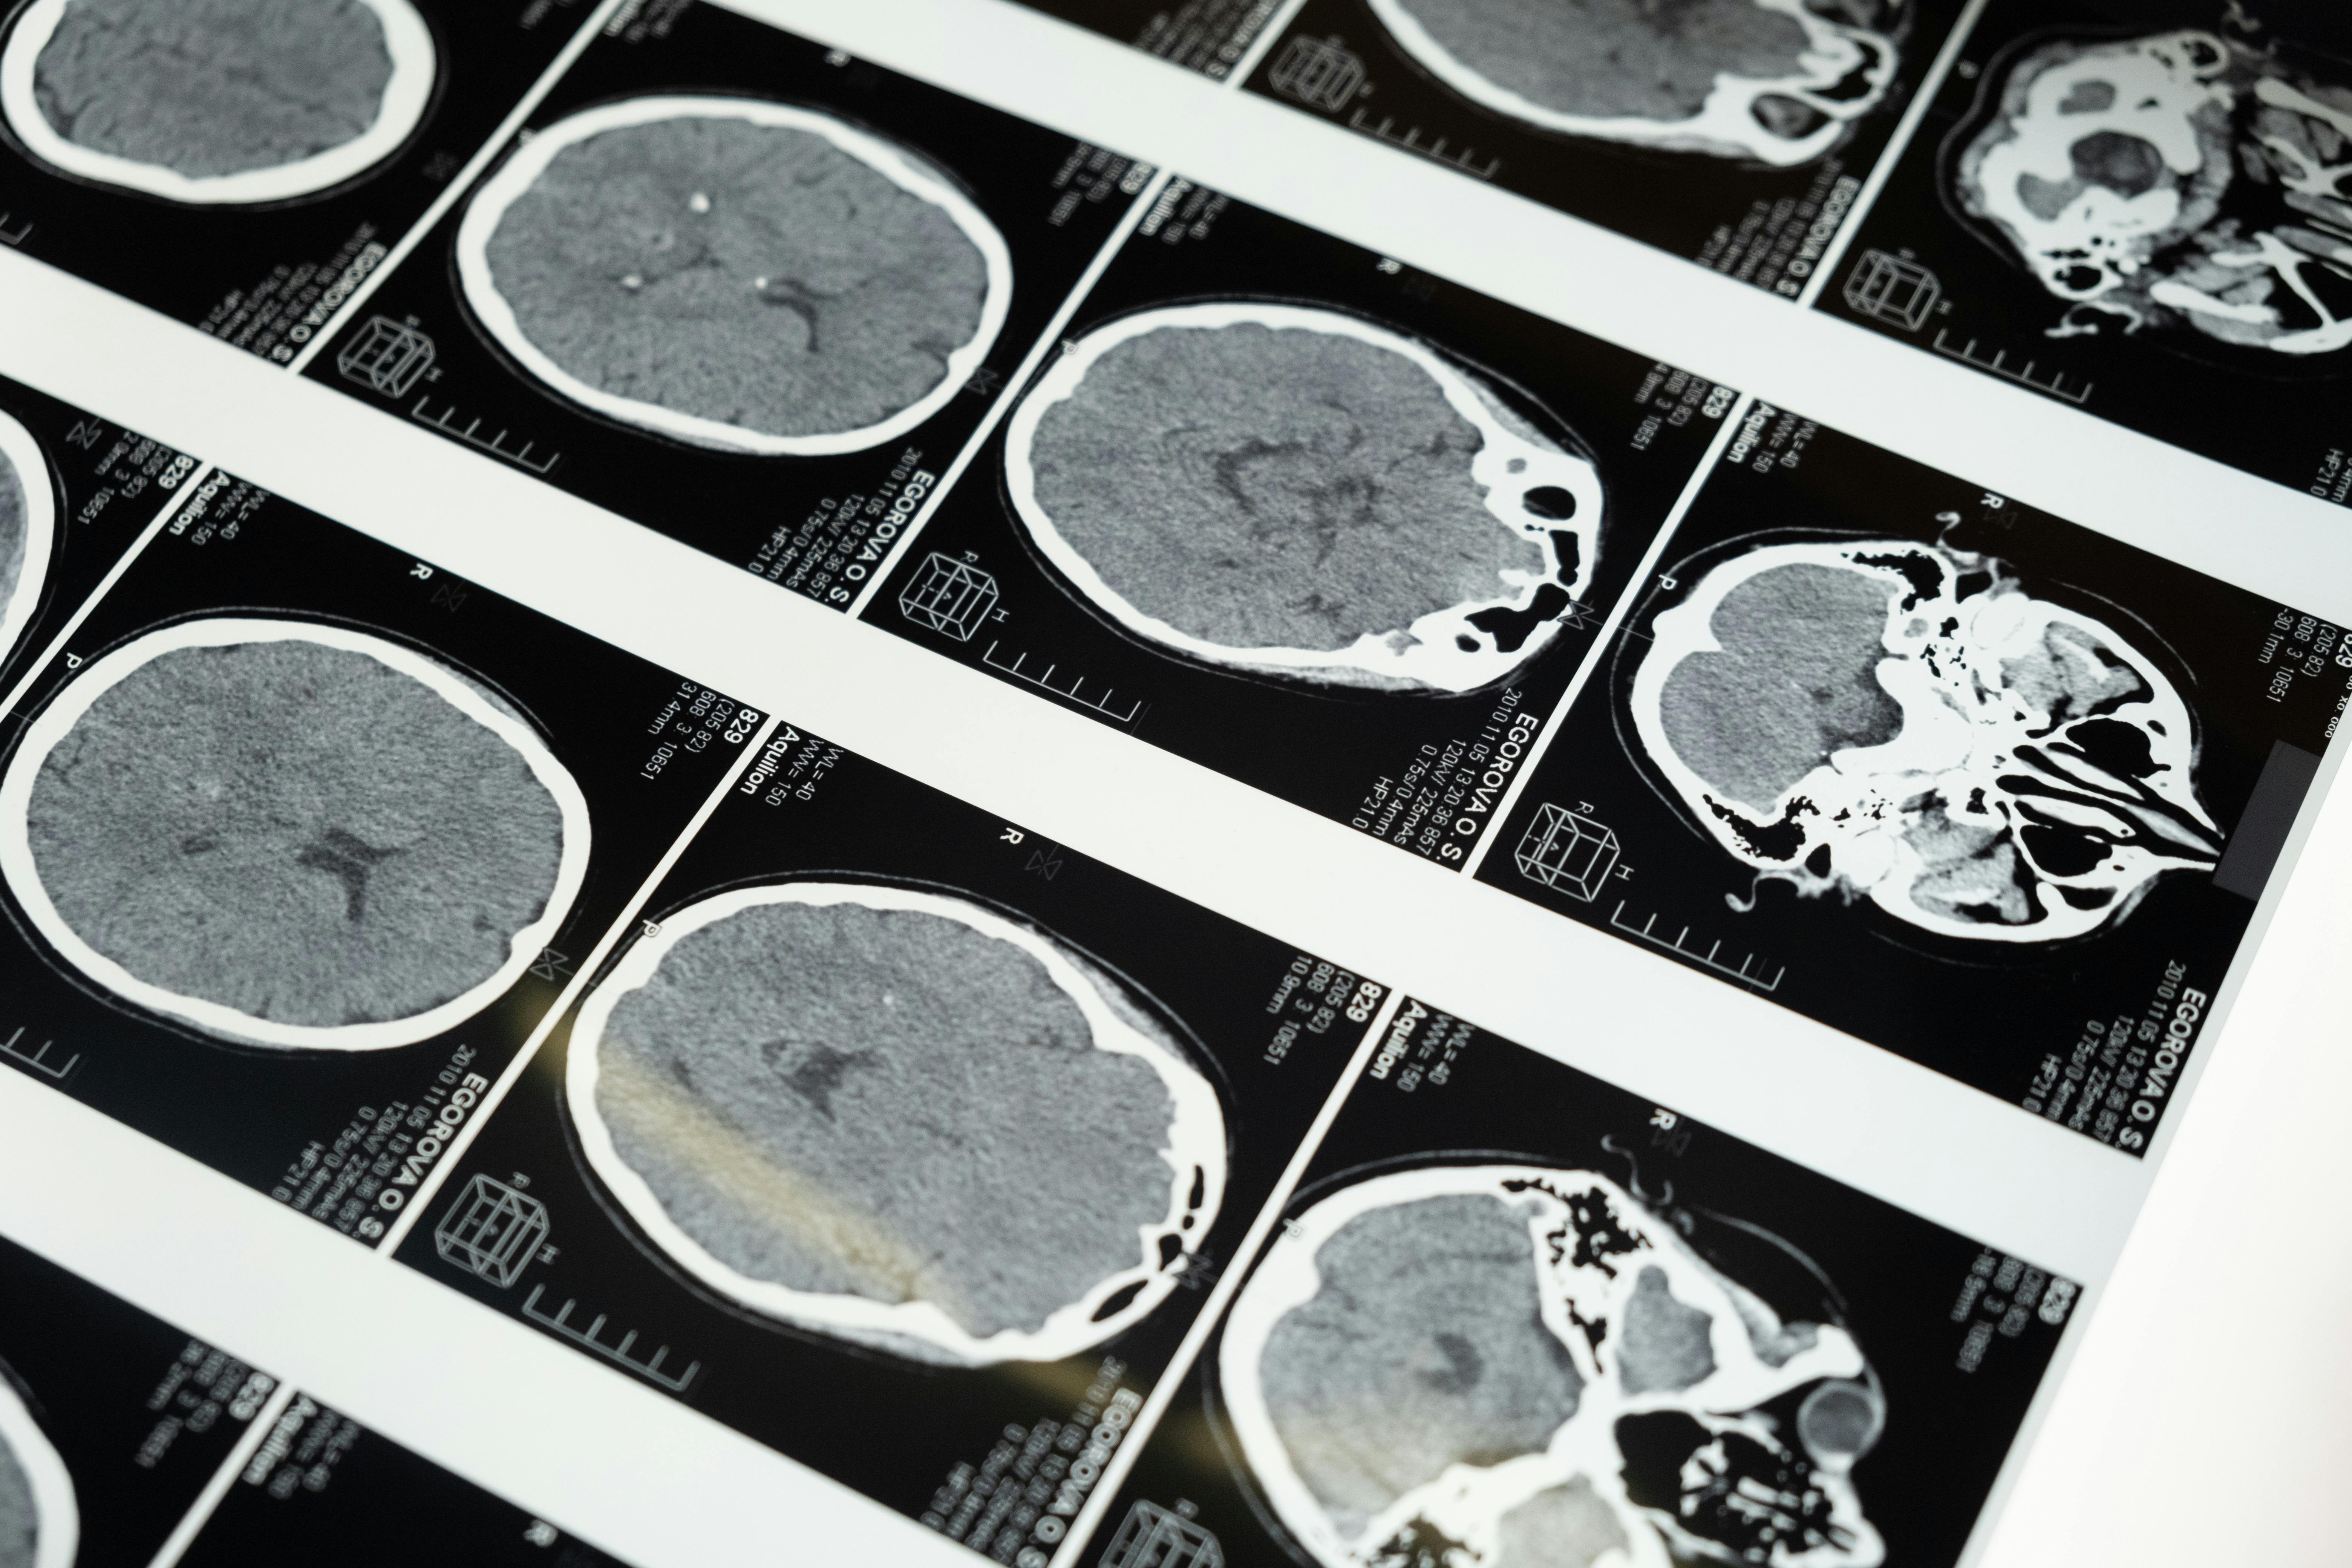

Doenças priônicas afetam o cérebro. São raras, mas perigosas.

O que acontece no cérebro

Com o tempo, esses “blocos” mal dobrados se juntam e formam agregados. Eles são rígidos, parecidos com fibras. No tecido, vemos lesões microscópicas que lembram uma esponja. O resultado é perda de neurônios e de funções cerebrais.

Por muito tempo, o diagnóstico definitivo era neuropatológico, ou seja, após o falecimento do paciente analisava-se tecido cerebral. Mas precisávamos de ferramentas confiáveis em vida. Durante anos, nos guiamos por sinais clínicos, ressonância, eletroencefalograma e marcadores como a proteína 14-3-3 no líquor. Eles ajudavam, mas não eram específicas o suficiente.